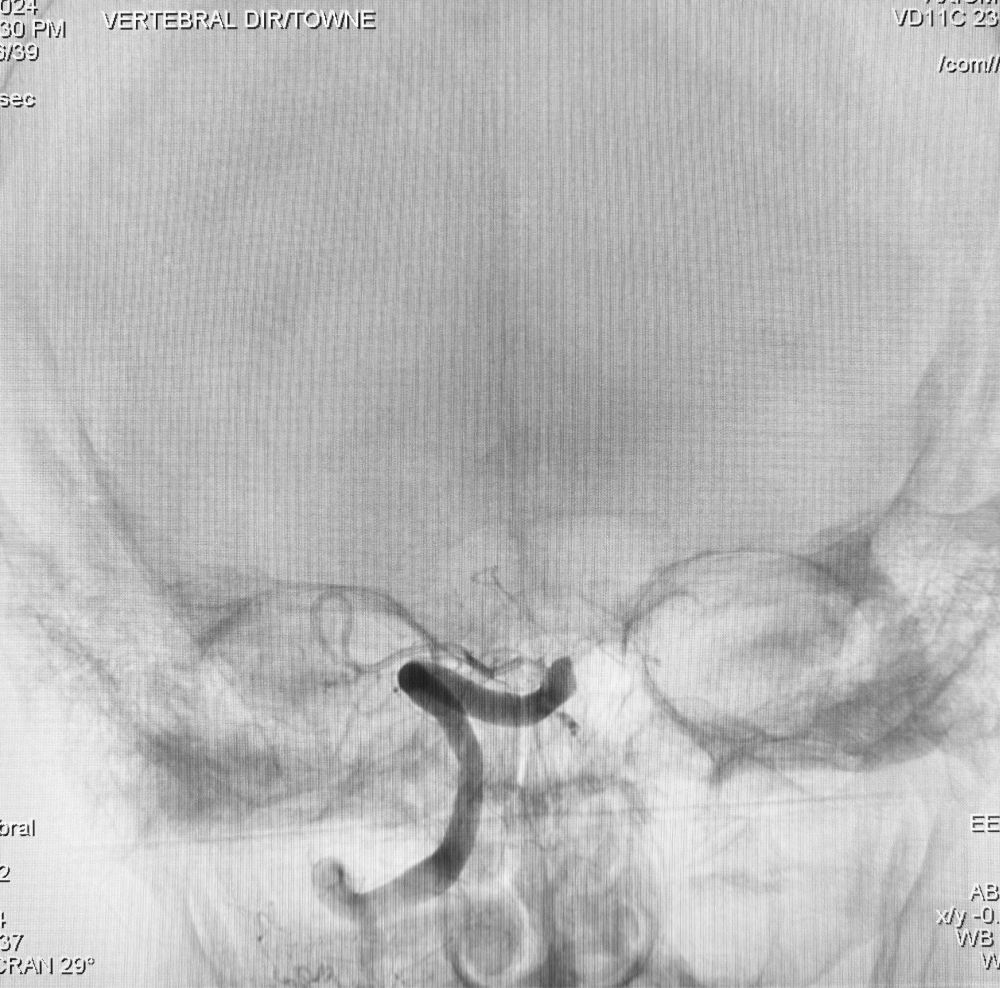

O q deu trabalho passar esse fiapo de artéria pra fazer a angioplastia de carótida não tá escrito

São 2 aneurismas em posições bem semelhantes. Um tem 1mm e o outro 1cm. Qual desses 2 aneurismas vc acha tem maior chance de romper e dar uma hemorragia? E qual deles provoca uma hemorragia maior? E ainda, qual deles é mais difícil de tratar?